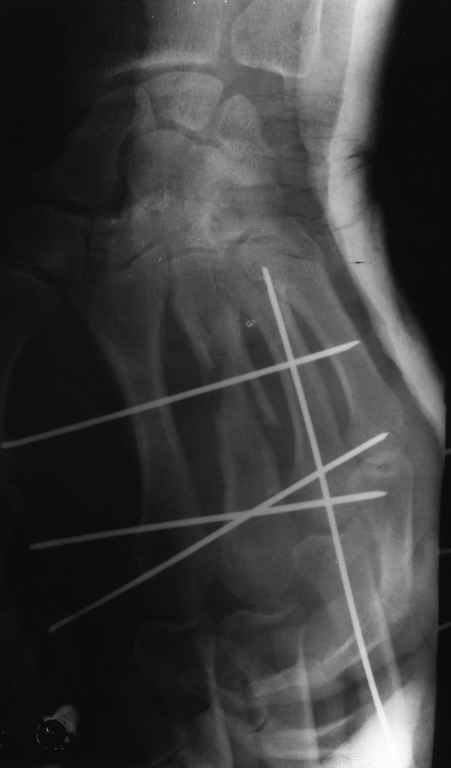

Диагноз: Стойкая Смешанная дермотеногенная контрактура 3,4 пальца правой кисти.